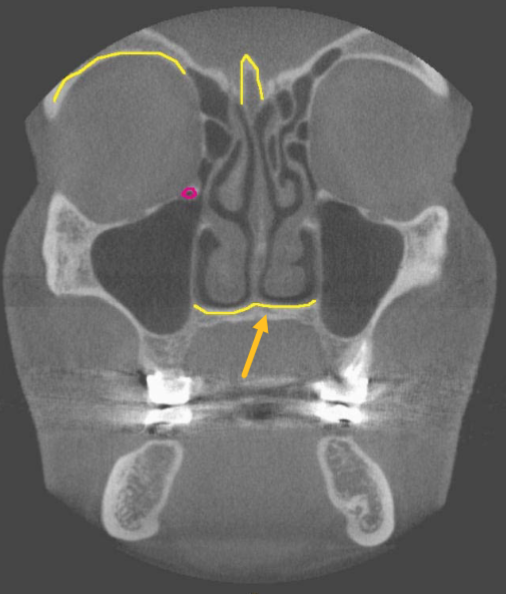

mental foramen

what is the structure indicated by the arrow

hard palate

identify the structure

nasal floor

identify the structure indicated by the ARROW